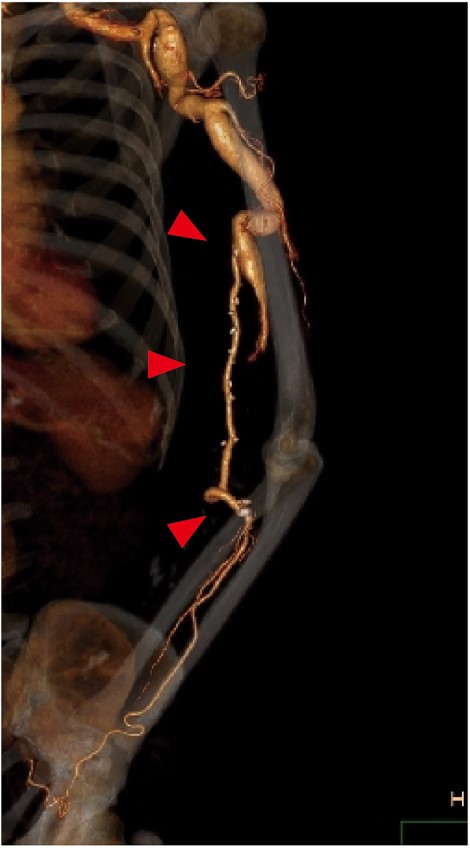

Follow-up CT showed patency of the great saphenous vein graft (Fig. 3), and vascular Doppler ultrasound indicated a sufficient palpable pulse in the radial artery, with the latter finding confirmed when the elbow was flexed 90 degrees. The postoperative course was uneventful. At 1 year after surgery, the patient was asymptomatic and graft patency was confirmed by an ultrasound examination.

Postoperative contrast CT showing the patent great saphenous vein graft (red arrows) anastomosed from the brachial to ulnar artery. To prevent graft occlusion due to elbow flexion, the graft was routed through the ulnar side of the elbow.